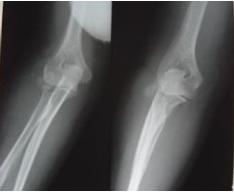

桡骨小头骨折是常见的肘部损伤,占全身骨折的0. 8%,约有l/3患者合并关节其它部位损伤。桡骨小头骨折是关节内骨折,如果有移位,理应切开复位内固定,恢复解剖位置,早期活动,以恢复肘关节伸屈和前臂旋转功能。